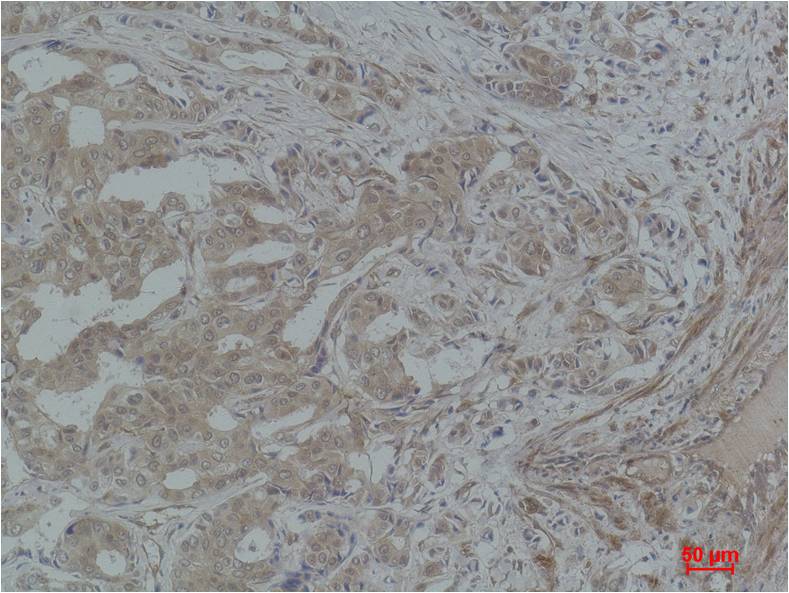

STAT3 Rabbit pAb

Product name: STAT3 Rabbit pAb

Reactivity: Human

Alternative Names: APRF antibody, HIES antibody, Signal transducer and activator of transcription 3 antibody

Dilutions: WB 1:1,000-2,000??? IHC? 1:200-500

Immunogen: Recombinant Protein

Observed Band: 79,86kDa

Cellular localization: Cytoplasm,?Nucleus

Background: Signal transducer and activator of transcription 3, also known as STAT3, is a transcription factor which in humans is encoded by the STAT3 gene. Stat3 is constitutively activated in a number of human tumors and possesses oncogenic potential and anti-apoptotic activities.